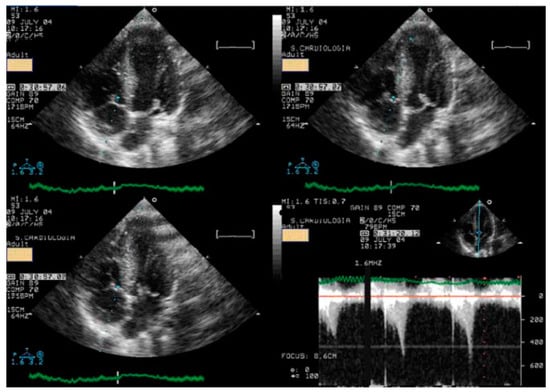

Children underwent treadmill exercise tests guided by symptoms using the standard Bruce protocol [22]. A modified version of the Bruce protocol was utilized to facilitate the assessment of Doppler parameters, providing a simpler evaluation compared to the classical Bruce protocol. Standard twelve-lead electrocardiographic monitoring was conducted, with measurements of ST-segment alterations and any arrhythmias, heart rate, and blood pressure taken at baseline and each stage of the exercise protocol. Before the exercise test, a baseline echocardiogram was performed with the child in the left lateral decubitus position for initial assessment. This involved acquiring 2D and M-mode images in at least four planes: parasternal long- and short-axis and apical four- and two-chamber views (with Doppler parameters evaluated and stored based on clinical requirements). During the exercise test, two-dimensional echocardiographic images were obtained from the parasternal long- and short-axis and apical four- and two-chamber views, with the child in a standing position at rest, during exercise (see Figure 1), at peak exercise, in the immediate post-exercise period, and during recovery [1].

Figure 1.

Image acquisition in the orthostatic position during exercise stress echocardiography using a treadmill for a 17-year-old boy with chest pain related to exercise.